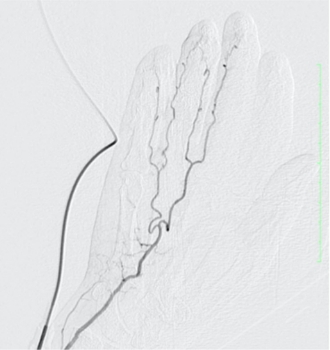

「モヤモヤ血管」とは、慢性的な痛みやこりの原因となる「異常な炎症血管」をわかりやすく表現した呼び方です。血管造影検査で見ると、この血管がモヤモヤとした状態で写っているため、このような名前が付けられました。

動注療法では、エコーを使用して手関節または足関節付近の動脈に細い針を刺し、溶けにくい薬液を注入します。この薬液が「モヤモヤ血管」のみを減らし、痛みを取り除くことを目的としています。

※症例の提供:オクノクリニック様